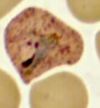

What form of plasmodium spp is being shown here?

Band form of P. malariae Think of this one as the "gigolo" of the spp because it likes older red cells so they wil be SMALLER **Band form is pathognomonic!** **Mature form will have 8-12 merozoites rosetting with PIGMENT**